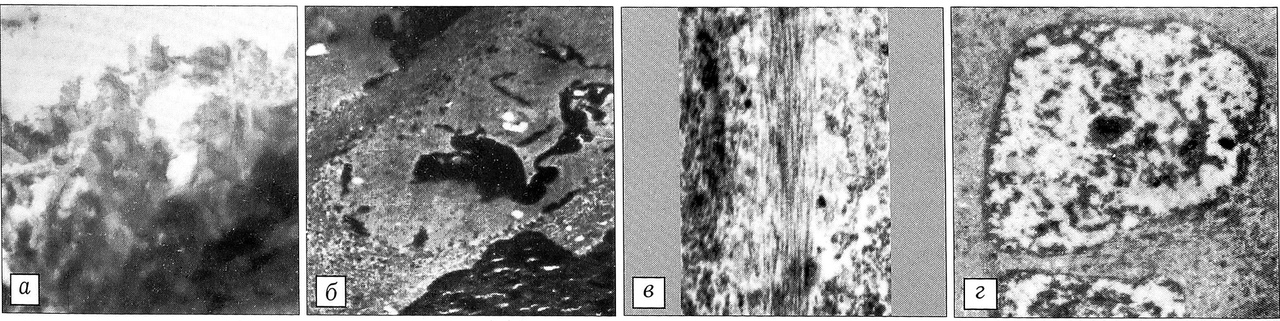

Рис. 2. Ультраструктурные изменения суставного хряща на 7-й день после воздействия лазерного излучения. ТЭМ. a — разрыхленная поверхность суставного хряща в пограничной с дефектом зоне (ув. 20000); б — коагулированные органеллы хондроцитов в пограничной с дефектом зоне (ув. 3000); в — коллагеновые фибриллы поверхностного слоя хрящевой пластинки в прилежащих к зоне воздействия участках (ув. 12000); г — хондроциты поверхностного слоя, расположенные в участках, прилежащих к пограничной зоне (ув. 3000).

Изучение в ТЭМ ультратонких срезов нагружаемых и не нагружаемых участков хрящевой пластинки показало, что через 7 дней после лазерного воздействия в пограничной с дефектом зоне поверхность суставного хряща разрыхлена. Коллагеновые фибриллы хрящевого матрикса, лежащие под поверхностным слоем, имеют плотную гомогенную структуру (рис. 2, а). В лакунах хондроцитов всех слоев хряща видны лишь небольшие остатки коагулированных клеточных элементов (рис. 2, б). Края костных структур подлежащей субхондральной кости выглядят «оплывшими». Сам дефект содержит белковые массы, тонкие волокнистые структуры и остатки обуглившихся тканей. В участках, прилежащих к пограничной зоне, в поверхностном слое хряща наряду с дистрофически-измененными волокнистыми структурами определяются поперечноисчерченные коллагеновые фибриллы, располагающиеся параллельно поверхности. Их внутренняя тонкая структура сходна со структурой неизмененных коллагеновых фибрилл хрящевого матрикса нормального суставного хряща (рис. 2, в). В хондроцитах этих участков хрящевой пластинки продолжают выявляться дистрофические изменения в виде уплотнения цитоплазматических и ядерных структур (рис. 2, г). Иногда среди уплотненных цитоплазматических органелл встречаются мелкие одиночные канальцы гранулярного эндоплазматического ретикулума.